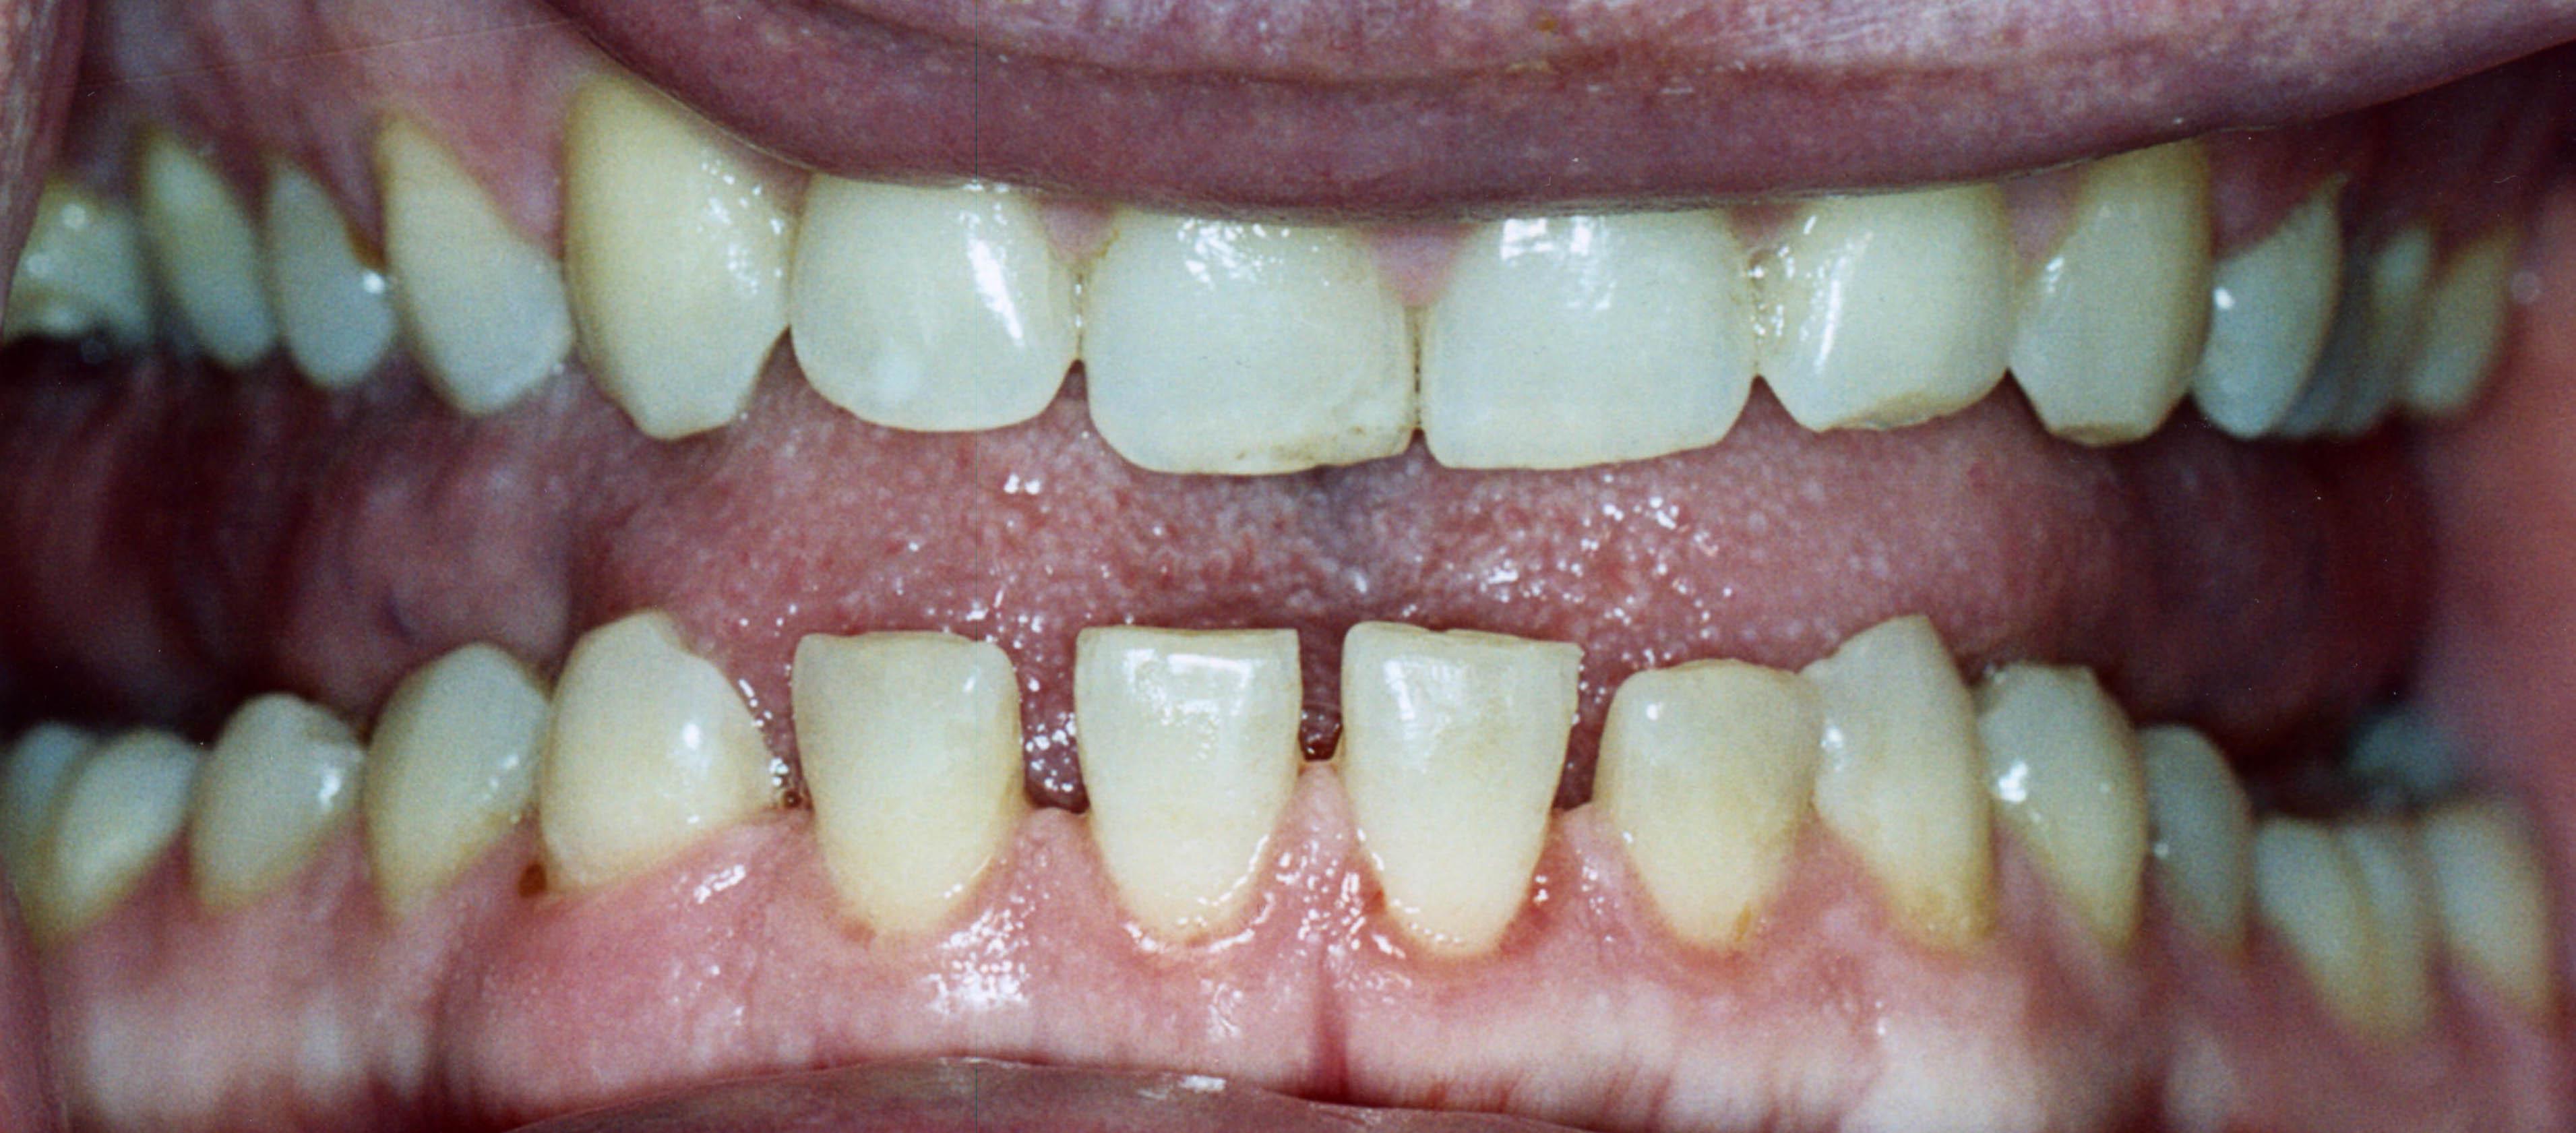

手腳異常腫大或臉形改變可別大意,可能是肢端肥大症惹禍,尤其早期症狀表現不明顯且病程緩慢,導致許多患者誤以為是正常老化,後續可能衍生包括心臟肥厚、心臟衰竭或肝臟肥厚、骨骼軟組織增生肥大等問題;臺大醫院內科部副主任暨代謝內分泌科主任王治元教授指出,肢端肥大症大多是因為腦下垂體分泌過多生長激素所造成,若發生在成年人身上,因生長板已閉合,就會造成骨骼異常增生,像下巴或前額突出、牙齒裂開等現象,可透過抽血做初步的篩檢。

肢端肥大症若發生在成年人身上,因生長板已閉合,就會造成骨骼異常增生,下巴或前額突出。

因下巴突出,下排牙齒亦被拉開變疏。